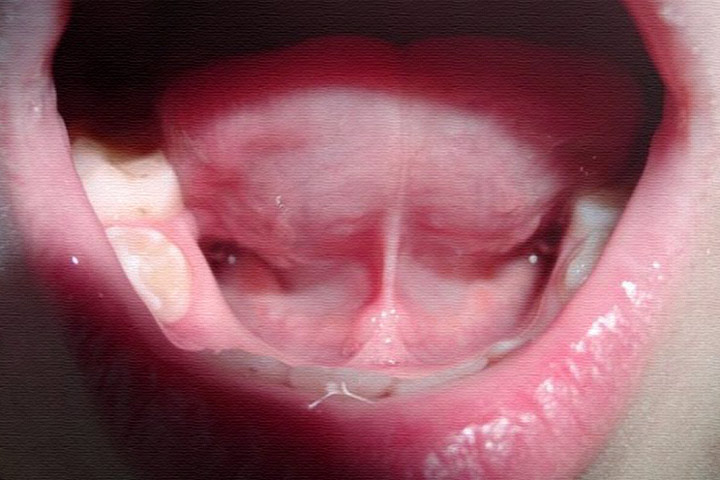

Исключение: подрезание подъязычной связки – манипуляции нужны сразу же, иначе появится рубец.

В некоторых случаях необходимо растяжение подъязычной связки. Для этого кончик языка поднимают наверх, двумя пальцами нежно скользят по уздечке, чуть-чуть натягивая ее. Важно чтобы это не вызывало чувство боли!